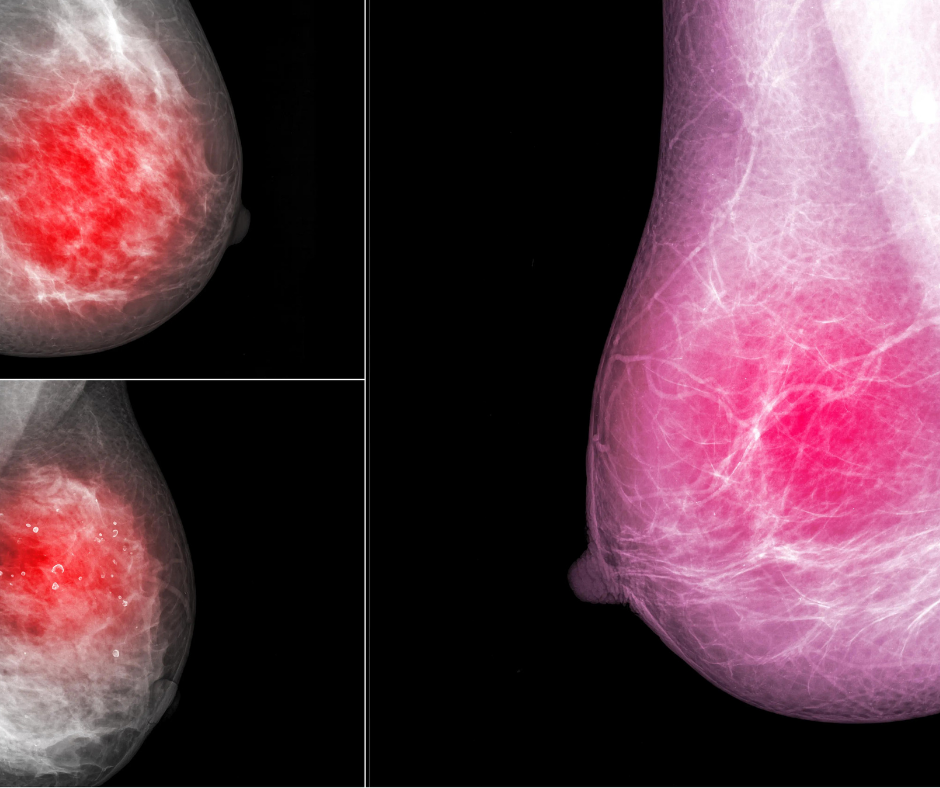

Diffusion-weighted imaging may be useful as a safe and effective screening tool to supplement mammography in women with dense breast tissues.

Following breast cancer treatment, women who have access to breast MRI may safely forgo additional mammographic or digital breast tomosynthesis follow-up.

Breast ultrasound/MRI fusion significantly improves localization of incidentally detected MRI lesions which are occult on an initial ultrasound survey alone.

Nonsuppressed background parenchymal enhancement could indicate patients who will show inferior response and allow for a personalized redirection of treatment.